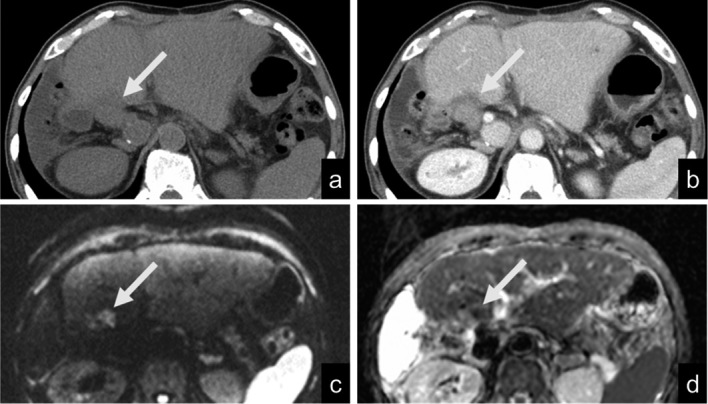

Distinguishing recurrent cholangiocarcinoma lesions from postoperative fibrosis or biliojejunostomy lesions using contrast-enhanced computed tomography (CECT) alone is challenging. This study examined the value of adding diffusion-weighted magnetic resonance imaging (DWI) to CECT for the detection of cholangiocarcinoma recurrence. This single-institution retrospective analysis included 33 patients who underwent cholangiocarcinoma resection between January 2016 and December 2020. Of the patients, 20 were in the recurrence group and 13 were in the non-recurrence group. Two observers independently reviewed the CECT images and subsequently reviewed the combined CECT and DWI images (b-value, 1000 s/mm2), with each image reviewed twice. The diagnostic performance was evaluated using receiver operating characteristic (ROC) curve analysis. Kappa statistics were used to evaluate agreement. The diagnostic performance (area under the ROC curve [AUC]) of both observers improved after the addition of DWI; the AUC improved from 0.614 to 0.918 (P = 0.003) in the first session and from 0.820 to 0.928 (P = 0.20) in the second session for Observer A, whereas it improved from 0.566 to 0.858 (P < 0.001) in the first session and from 0.753 to 0.930 (P = 0.02) in the second session for Observer B. The intraobserver and interobserver agreements improved after the addition of DWI; the kappa value improved from 0.586 to 0.656 for Observer A, from 0.371 to 0.838 for Observer B, from 0.308 to 0.766 in the first session, and from 0.464 to 0.620 in the second session. Adding DWI to CECT improves the detection of cholangiocarcinoma recurrence compared to CECT alone.